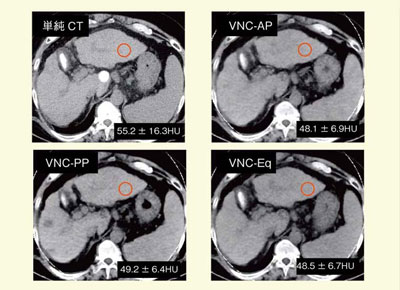

肝細胞がん(HCC)の動脈相画像からVNCを作成した(図4)。VNCでも,肝細胞がんは背景肝に比べて低吸収域として認識できる。同時に作成できるヨードマップでは,造影剤の取り込みから多血性病変であることが明らかである。また,動脈相のほかに,門脈相,平衡相のVNCを作成し,同じ場所にROIをとってCT値を比較したところ,非常に均質な値が測定され,信頼性が高いことが証明された(図5)。そのほか,大動脈の石灰化(図6)や体内金属,脂肪肝などが良好に認識可能であり,石灰化とリピオドールの区別にも有効であった。

VNCで単純CTを省略できれば被ばく低減につながることが示唆されているが,腎臓ではすでに,腫瘤性病変の検出能に関して有効性を認める論文(Grsser,A.,et al.Radioligy,252,2009.)が発表されている。肝臓では,背景肝と病変部の微妙な濃度差を認識することが診断の手がかりとなる場合もあるため,VNCで単純CTが省略可能かどうか,今後の検証が待たれる。

![]() 図4 肝細胞がん(HCC)の動脈相画像から作成したVNC |

![]() 図5 単純CTとVNCの背景肝臓CT値の比較 |